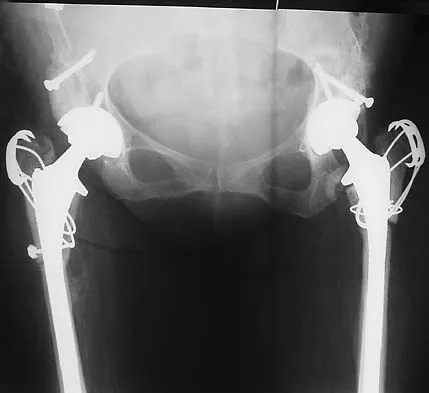

Figures 40a and 40b show the pre- and postoperative radiographs of an 82-year-old woman with bilateral hip pain who has had staged total hip arthroplasties. To minimize potential injury to the sciatic nerve at the time of surgery, the surgeon should

Explanation

To improve hip biomechanics and secure more suitable bone for acetabular fixation, the true acetabulum is often resurfaced in patients who have developmental dysplasia of the hip, thus lowering the hip center and lengthening the leg. Acute lengthening of more than 3 cm will place excessive tension on the sciatic nerve and require a femoral shortening to avoid sciatic nerve injury. The other maneuvers will not relieve sciatic nerve tension because of limb lengthening. Koval KJ (ed): Orthopaedic Knowledge Update 7. Rosemont, IL, American Academy of Orthopaedic Surgeons, 2002, pp 430-431.